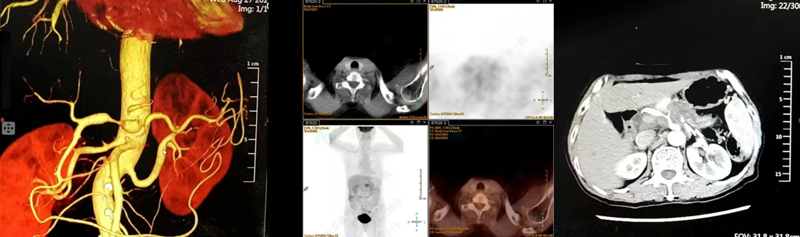

患者术前影像▲

患者女,63岁,以“全腹部不适2月”主诉入院,2月前饮食后出现全腹部不适,以右侧为主,腰背部疼痛,无恶心、呕吐,无反酸烧心等不适,外院行胸部及腹部CT示:双肺间质性改变,气管憩室可能,右侧第7肋骨陈旧性骨折可能,胰腺体尾部恶性占位,考虑胰腺癌可能,腹膜后稍大淋巴结,胆囊显示不清,胆总管扩张。术前检查发现病灶位于胰体尾部,大小为头足距3.5cm,左右距3cm,胸背距3cm。